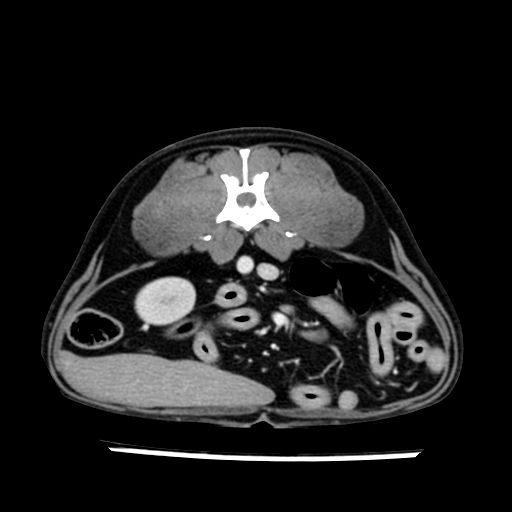

prescritto esame TAC

sequenza immagini limitata al fegato reni e surreni

le immagini ecografiche rispetto alla tac datano circa 7 mesi prima ,le surrenali sono normali nonostante il test acth sia risultato positivo .all’esame TAC dopo diversi mesi risultano aumentate armonicamente nel volume e si individua un forte sospetto di adenoma ipofisario .

sospetto adenoma ipofisario vs. meno probabilmente meningioma della base; intertiziopatia polmonare; lesione espansiva epatica, verosimilmente del lobo laterale sinistro, di sospetta natura neoplastica; lesioni spleniche di natura da definire; iperplasia/ipertrofia delle ghiandole surrenali, bilateralmente; vertebra di transizione del rachide toracico; tenosinovite cronica del muscolo bicipite brachiale di destra.